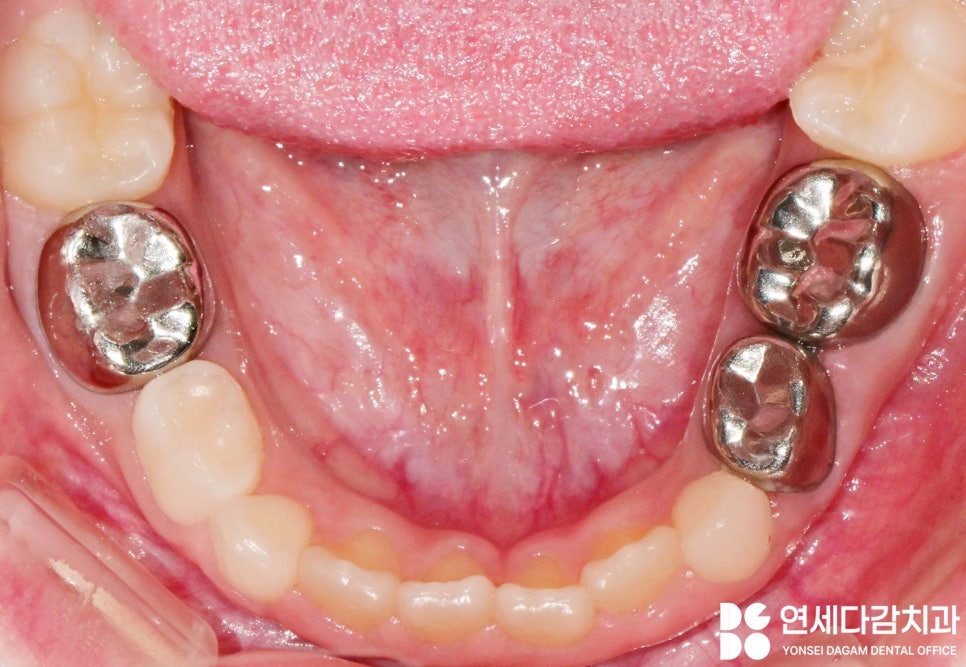

마취 후 가능한 손상이 없도록 크라운을

제거한 뒤 새로 제작합니다.

기존 크라운을 조심스럽게 제거하고

치아 상태를 정확히 평가한 후

새로운 크라운을 맞춤 제작합니다.

그 결과 통증과 고름이

해소될 수 있게 됩니다.